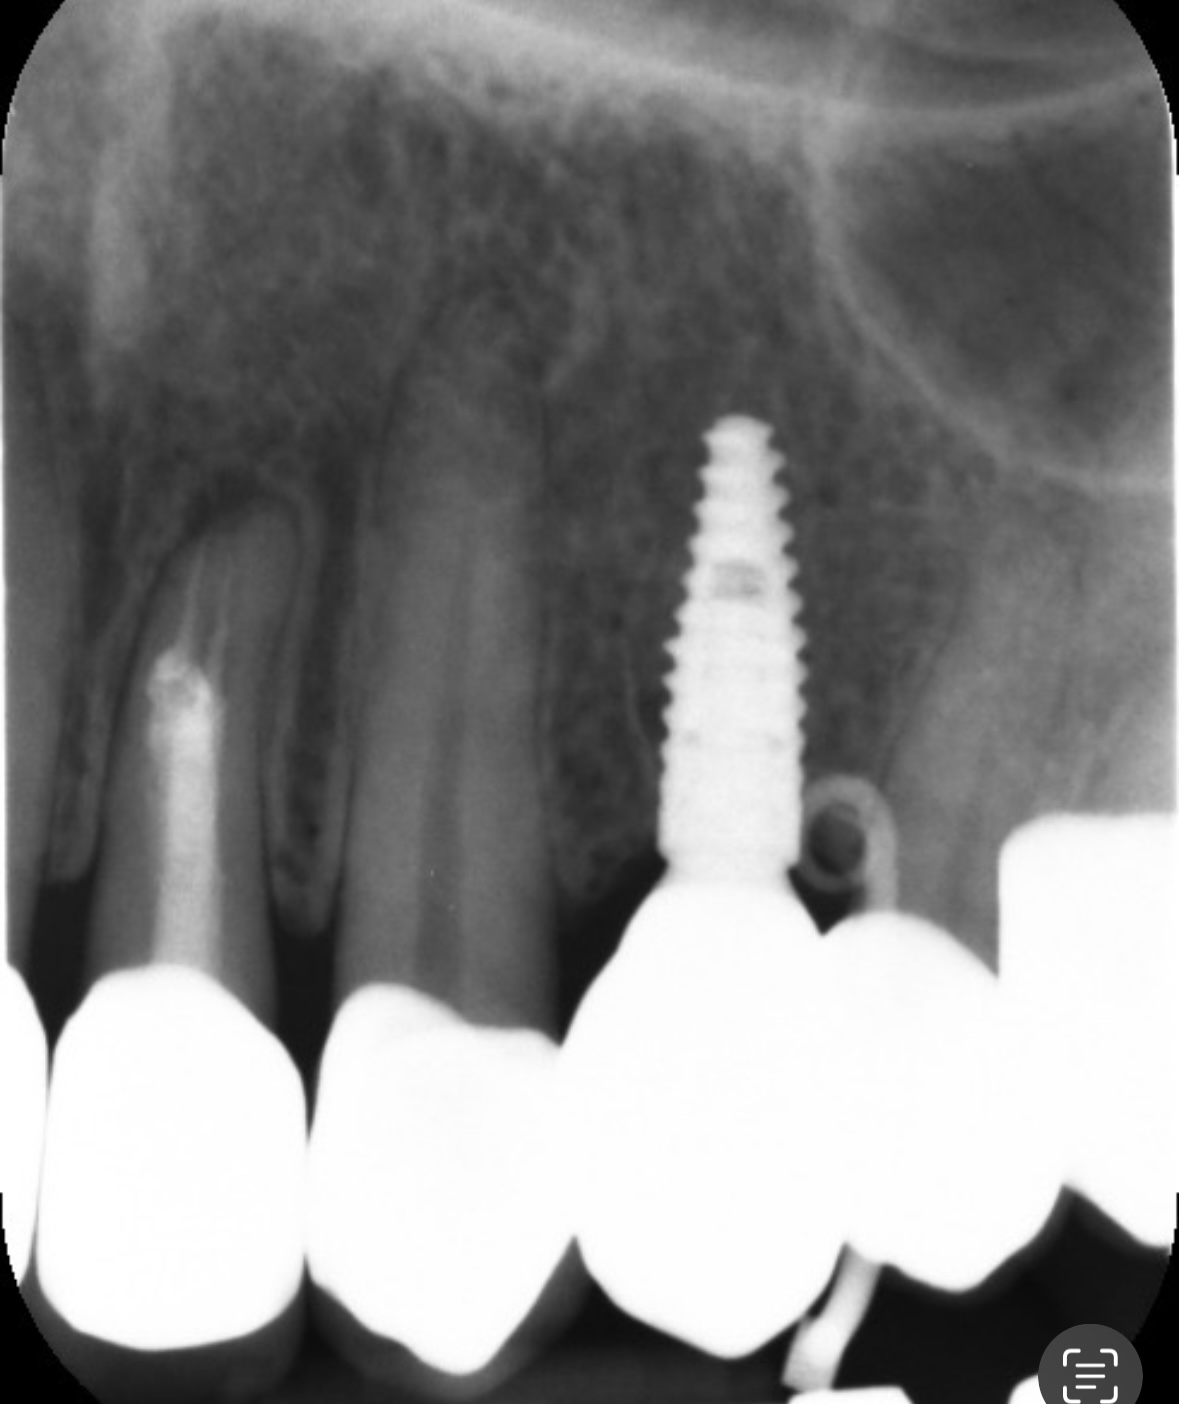

今日また歯医者さんに行き、針のような器具を挿入した状態でレントゲンを撮ってもらいました。

その結果、針がインプラントの手前で曲がっていたため、原因はインプラントの歯ではなく、別の歯にあるとのことでした。

先生のお話では、このできものはフィステルであるとのことで、原因としては側切歯の根の部分に炎症があるのでそこの歯からの可能性が高いそうです。

画像1

画像2

よく見ると第一小臼歯でしたね。

たまたま根管治療してある側切歯の根尖も、問題がありそうだなとわかったのでしょうか。